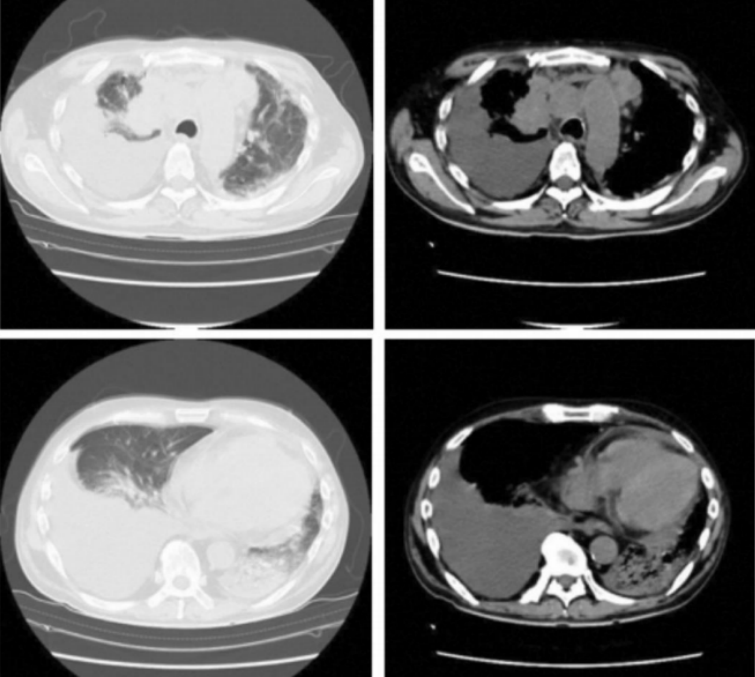

军团菌肺炎的临床表现缺乏特异性,发病缓慢、干咳、疲劳、头痛、喉咙痛、肌痛和不适。症状与肺炎链球菌肺炎或其他细菌性肺炎类似,常伴有肺外表现,包括神经精神症状、消化系统症状、肝肾功能损伤、低钠血症等表现。该病很难诊断,出现下列症状时应高度怀疑军团菌肺炎:①相对缓脉,高热;②不明原因的肺外症状,如伴有腹痛、腹泻等消化道症状或意识障碍等神经系统症状;③急性肝肾功能损伤、低钠血症、低磷血症;④痰涂片或痰培养阴性;⑤使用β-内酰胺类抗生素、氨基糖苷类抗生素治疗无效。当患者肺外表现严重而肺部表现并不明显时,更容易漏诊,延迟治疗则会显著影响患者的预后。关于癌症患者中军团菌肺炎的非典型表现的研究相对较少,大多数关于军团菌肺炎的研究主要集中在一般人群中的典型表现和传播途径,尤其由非嗜肺菌株引起的军团菌感染,特征不典型,包括无症状或轻度临床症状,与其他常见的机会性感染影像学特征难以区分。免疫功能低下尤其是移植受者,尽管临床表现与其他细菌性肺炎相似,但腹泻通常很突出,也可呈急性过程,病情凶险。即使不存在环境因素情况下,也可以发生军团菌肺炎。既往一项研究探讨了癌症患者中军团菌肺炎的非典型表现,该研究回顾性复习了1999年1月1日至2013年12月31日这15年间在一癌症中心(MSKCC)诊断的40例军团菌肺炎患者的临床资料,其中嗜肺军团菌31例(31/40,77.5%),非嗜肺军团菌9例,多数军团菌肺炎发生于血液系统恶性肿瘤患者或干细胞移植(SCT)受者。影像学表现多样,结节性军团菌肺炎均偶然发现或有一惰性临床过程。基于患者的影像学特征的临床特征分为结节性军团菌肺炎和非结节性军团菌肺炎,对于实体肿瘤患者,很多患者可能没有结节样改变,而血液系统肿瘤和器官移植患者以及中性粒细胞减少患者,多出现结节样改变。非结节样改变可能是嗜肺军团菌肺炎,而结节样改变可能为非嗜肺军团菌肺炎。没有症状的患者结节性改变多见,而有症状的患者非结节性改变多见。此外,研究还发现军团菌肺炎在夏季多发。因此,在免疫功能低下患者,特别是血液系统恶性肿瘤患者和SCT患者的肺结节性病变,鉴别诊断时应考虑军团菌肺炎,影像学表现为结节性改变的患者多与非嗜肺菌株有关。病例:男,57岁“发热及呼吸困难”半天。有饮酒史,无心脏疾病和糖尿病。5个月前诊断为右上肺叶腺癌,肿瘤分期为cT4N3M1c IVB,心包、胸膜转移和多发性骨转移。免疫或培美曲塞化疗的第一个周期引起的药物性肺炎,4个月皮质类固醇治疗。强的松龙60 mg/d,然后逐渐减少。入院时每天使用地塞米松2 mg。给予卡铂和紫杉醇作为二线化疗两个周期。最后一次化疗在入院前1个月。入院后查尿抗原军团菌阳性,肺炎链球菌阴性。尽管有上述结果,仍静脉注射哌拉西林/他唑巴坦+地塞米松。患者入院当天意识恶化、插管、房颤、心脏骤停,心肺复苏后给予左氧氟沙星,心率恢复正常,住院后第2天死亡。未尸检。在患者去世后,痰培养分离出嗜肺军团菌血清1组;未检出其他病原体。由此可见,对于嗜肺军团菌,如果没有确切诊断,即使是责任菌,仍然非常凶险。患者的影像学可见胸腔积液,肺内渗出并不多。

军团菌肺炎的影像学表现不具有特异性,实变是其常见的影像学发现,相对特异性的表现为磨玻璃影中混杂着边缘相对清晰的实变影,各个肺叶均可受累,1/3的病例可合并胸腔积液。免疫抑制患者的影像学表现同样不具有特异性。前述研究回顾性复习了某一癌症中心确诊的40例军团菌肺炎病例,其中,8例表现为单发或多发结节【6例实性伴有磨玻璃晕征或空洞,2例实性结节,边界清楚,没有磨玻璃晕或空洞;6例为1~2个大结节,1例双侧随机分布的大量小结节,1例局灶性磨玻璃影伴微小结节。所有CT均显示结节性浸润,仅有4例(50%)在胸部X线检查中显示结节性浸润】,32例表现为混合性非结节性肺异常(包括肺叶实变、磨玻璃影、斑片状浸润),2例发现肺炎旁胸腔积液。下图A为70岁女性,右肺上叶实性结节伴磨玻璃晕;B为41岁女性,右上肺叶有实心结节;C为17岁男性,右中叶结节伴中央空洞,伴磨玻璃晕;D为51岁女性,舌叶结节,中心空洞,周围磨玻璃晕;E为35岁女性,右下肺叶结节和周围的磨玻璃晕;F为7岁女性,舌叶结节,中央有空洞。也有一些患者偶然发现结节状军团菌肺部感染,症状不明显。我科确诊的一例军团菌肺炎患者,男性,66岁,“咳嗽咳痰伴发热2周”,每日游泳,可能与污染水接触有关,影像学以渗出样改变为主。治疗过程中出现实变、多发结节样改变。军团病的诊断需要借助于有效的检测手段。常用的检测方法包括常规培养、尿抗原检测、核酸检测。培养仍然是诊断军团菌肺炎的“金标准”,但该方法具有滞后性,可能会延误诊断。尿抗原是作为一线的诊断测试,能够快速诊断,使患者得到及时治疗。但尿抗原仅能检出嗜肺军团菌1组菌株,敏感性只有75%,容易导致部分患者被漏诊。核酸检测费用比较高,敏感性高达90%。二代测序能为诊断提供更有效、更快捷的手段。1988年,Cunha教授率先提出了WUH评分系统:①体温>39.4℃;②CRP>187 mg/L;③PLT<171×109/L(如正常下限为125×109/L,则建议PLT<200×109/L);④Na<133 ldh="">225 U/L(339 U/L);⑥干咳(包括不咳嗽、少痰,多痰排除)。【注:每项1分,3分可能诊断,4分可能极大,5分以上确诊】